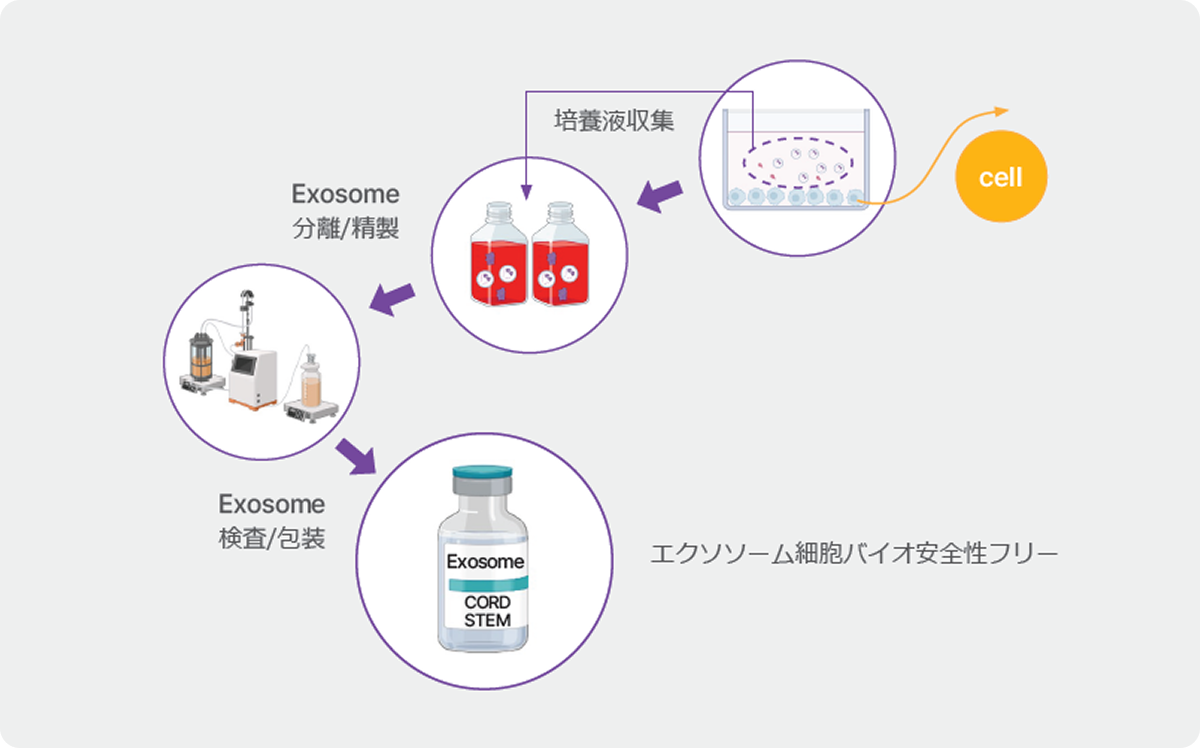

臍帯幹細胞由来上清液の特別な効果

・CHA 臍帯来幹細胞培養上清液の品質情報

| 由来細胞 | 臍帯由来幹細 (MSC) |

|---|---|

| ドナー人体由来ウイルスfree確認 | |

| 製造及び 工程 |

適正製造基準レベルの国内製造施設 |

| 高純度エクソソーム製造工程適用 | |

| 品質 | 50-200nm エクソソーム、 10億個/Vial |

| エクソソームマーカー – CD9、CD63、CD81など | |

| 機能マーカー – VEGF、HGF、BDNFなど (別紙参照) | |

| バイオ安全性 – 微生物、マイコプラズマ、エンドトキシン、ウイルスフリー |